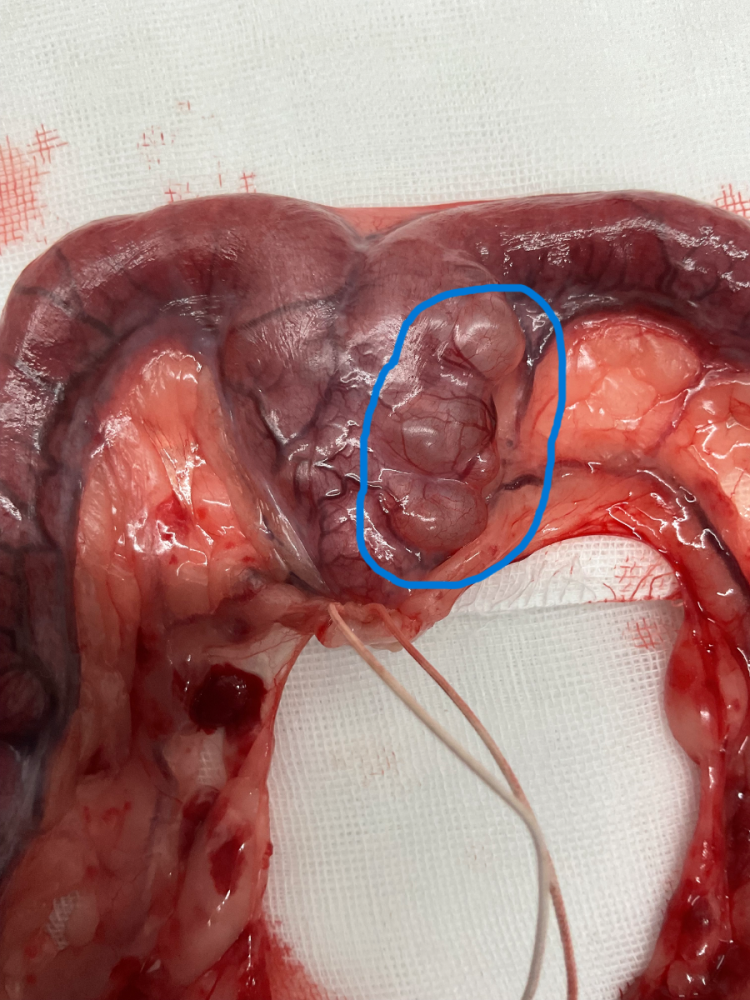

※拡大写真の青色の〇で囲っている箇所が嚢胞状の病変になります。

飼い主様とご相談のうえ、子宮・卵巣摘出手術(不妊化手術)を選択しました。また、嚢胞状の病変が悪性でないことを確認するため、摘出組織を病理組織検査に出しました。

結果は「腺筋症を伴う子宮内膜嚢胞状過形成」でした。

悪性所見はなく、子宮水腫の説明で触れた子宮内膜の肥厚に加え、性ホルモンの影響により子宮筋層内にも子宮内膜成分が形成されている状態でした。